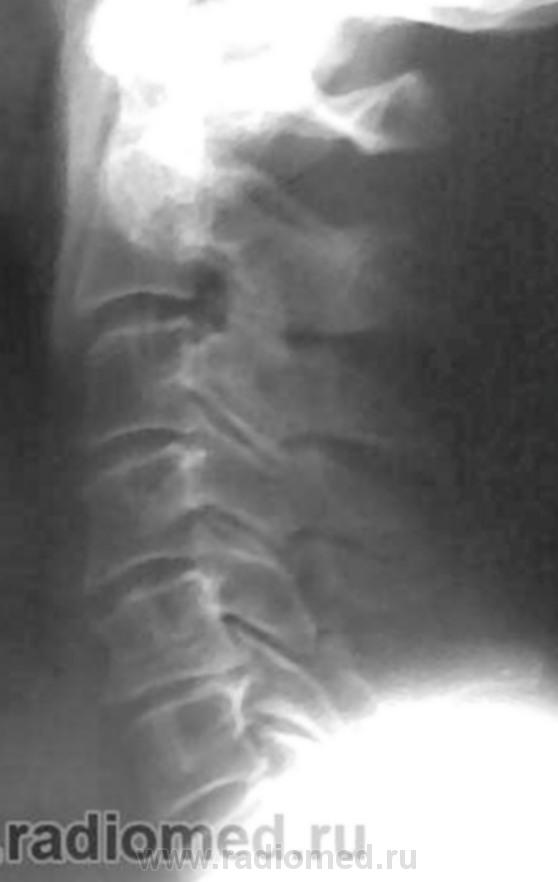

Остеохондроз, спондиллоартроз, протрузия МПД С5-С6 кзади. Что Вас смущает на этих снимках? Игра теней на уровне С6(прямой снимок)?

В теле С5 поперечное посветление в боковой, видимо и в прямой проекции.

Неоартроз+склероз обусловили линейные тени в проекции тела С5.

Переспав с мыслью родилась идея. Ведь пергрузочная болезнь может возникать и в телах позвонков. В теле С5 в данном случае зона просветления, которая не персекает полностью тело позвонка, а опоясывает, развиваясь под надкостницей. Края ее ровные, как бы поясок вокруг тела.Плотность тела позвонка увеличена, вероятно за счет компенсаторного капиллярного кровотока вокруг зоны перестройки. В данном случае, перегрузочная болезнь, вероятно, возникла как компенсаторный процесс в ответ на изменение оси нагрузки, либо, еще в молодом возрасте.как Признаю, игра теней и артроз не в тему.

На теле С5 вероятно изображение унко-вертебрального артроза. Это его законное место. В прямой проекции вообще толком ничего не видно. Снимки очень неважные. Почему ваши лаборанты так широко раскрыли диафрагму? Качество очень страдает. Если есть сомнения в бабочковидном позвонке, можно сделать прямую томограмму.

Для Goncharovakuraeva : я изменения описал как дистрофические, а посветление в теле С5, предположительно расценил как дисластические (типа фиброзной прослойки в теле позвонка).

Для Nela: я то же рассмтривал версию, что просветление в теле С5, за счёт унковертебрального артроза, но мне представляеться, что в последенем случае картина, несколько иная.